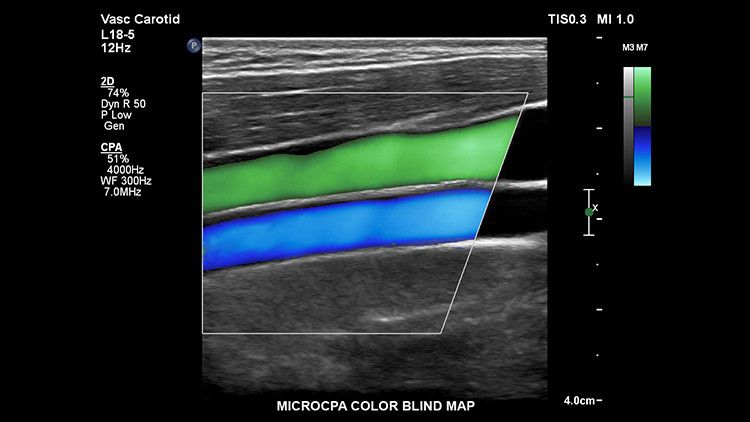

• Сосуды

ROI, IMT